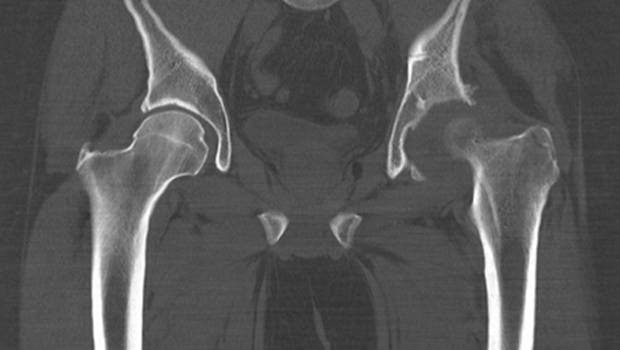

С помощью КТ тазобедренного сустава дают следующие оценки:

- состояния поверхности костей;

- состояния связок;

- наличия патологических проблем в суставе.

Иногда пациенты не знают что лучше: КТ или МРТ тазобедренного сустава? Все зависит от проблемы: если произошла травма костей, то более информативна КТ, а если проблема с мягкими тканями или развивается дегенеративное поражение суставов, то применяют МРТ, способную показать анатомические структуры. Но в большинстве случаев оба метода взаимодополняют друг друга.

Заболевания тазобедренных суставов, при которых применяют компьютерную томографию:

- артроз;

- остеопороз;

- ревматизм;

- травмы;

- опухоли;

- дисплазия.